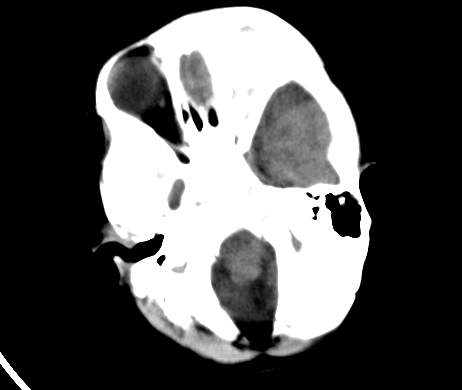

标题: PED1850:男 2岁 头部外伤1天,有事吗?

男 2岁 头部外伤1天,有事吗?科里意见不一 骨窗 没事,未上传